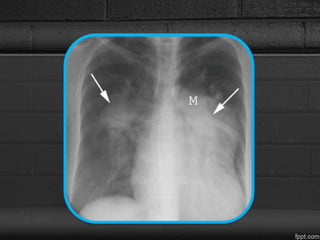

CXR

• Transverse diameter of the right interlobar

pulmonary artery, measured from the lateral aspect

of the vessel to its medial portion adjacent to the

bronchus intermedius, exceeds 15 mm in women

and 16 mm in men.

• The left pulmonary artery is best measured on the

lateral radiograph from the orifice of the left upper

lobe bronchus to the posterior aspect of the vessel;

when this measurement exceeds 18 mm,

pulmonary hypertension probably is present.